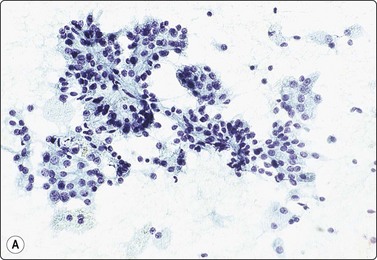

image image

Fig. 12.17 Renal cell carcinoma, papillary type

(A) Cell clusters and papillary fragments; small uniform nuclei; moderate amount of pale cytoplasm; some of the single cells are foamy macrophages (Pap, IP); (B) Poorly cohesive small cells with round uniform nuclei; stromal fragments from disrupted papillae; psammoma body lower left (DQ, HP).

Fig. 12.18 Renal cell carcinoma, papillary type

(A) Tumor cells strongly positive for CK7; same case as Fig. 12.17 (immunostaining, HP); (B) Tissue section from same case. Papillary pattern; interstitial foam cells; psammoma bodies (H&E, LP).

Papillary RCC type 2 can be mistaken for clear cell carcinoma due to higher nuclear grade and more abundant eosinophilic cytoplasm. It is CK7+ in only a small proportion of cases whereas most type 1 tumors are strongly positive. EMA is usually negative in type 2, positive in type 1 and in clear cell RCC. Prognosis is generally less favorable than for type 1 but varies with tumor size and nuclear grade.